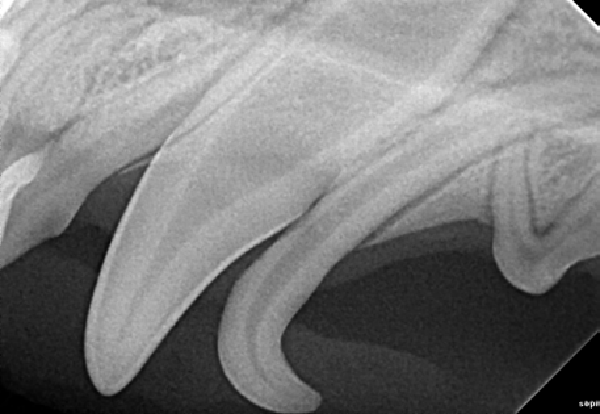

Figure 1A : Radiographie intra-orale de la première molaire mandibulaire droite d’un chien bichon de 6kg. L’examen radiographique est normal, il montre l’importance de l’espace occupé par les racines dentaire au sein de la mandibule chez un chien de petite taille.

Figure 1B : Radiographie intra-orale de la première molaire mandibulaire droite d’un chien croisé de 5 kg souffrant de parodontite très avancée. Une infection endo-parodontale est notable avec lyse osseuse alvéolaire marquée, la mandibule est fragilisée.